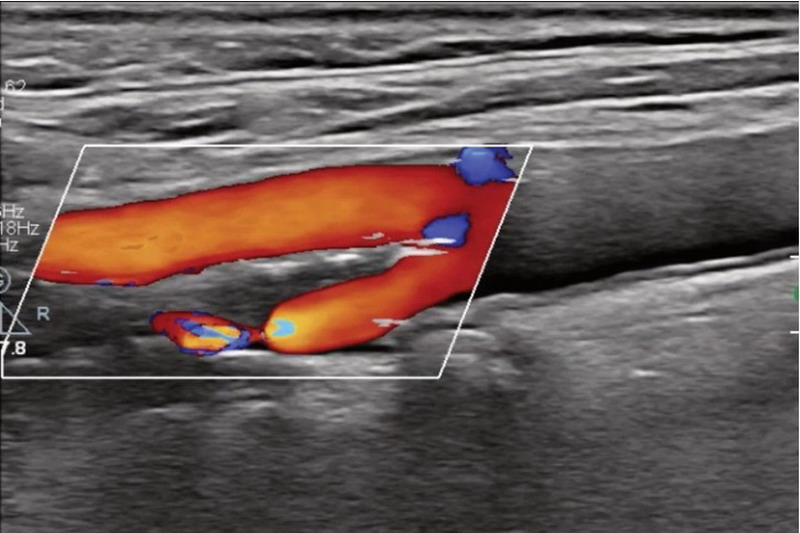

ECOGRAFIE DOPPLER ARTERIAL MEMBRE

Este o investigatie medicala nedureroasa, non-invaziva care evalueaza morfologia arterelor si vizualizeaza fluxul sanguin la nivelul arterelor.

ECOGRAFIA DOPPLER VENOS MEMBRE

Este o investigatie imagistica non-invaziva, nedureroasa care permite vizualizarea fluxului la nivelul venelor permitand diagnosticarea trombozei venoase (prezenta chegurilor-trombi) si a insuficientei venoase cronice.